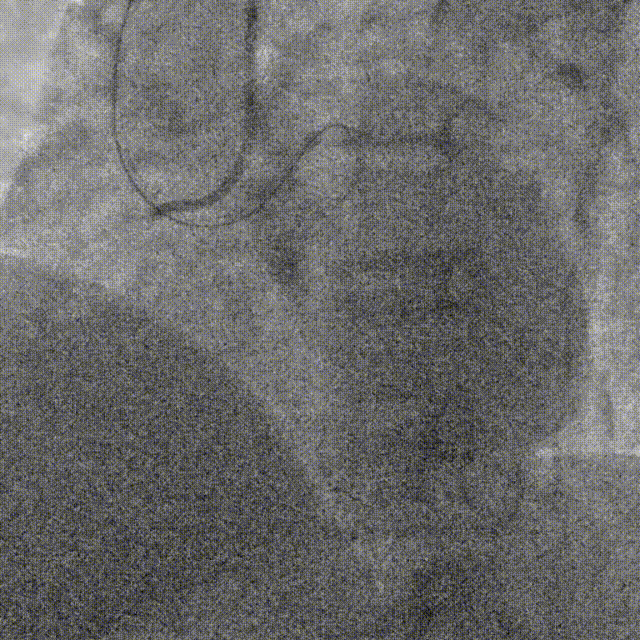

使用P200导丝攻击远端纤维帽前进困难,更换G3进入LAD近段内膜下,直接使用Telescope™导引延长导管辅助下AGT技术,r-CART后G3顺利进入Telescope™导引延长导管。

直接使用G3导丝rendezvous,球囊扩张后行IVUS检查确定血管直径及支架落脚点。

D1释放DCB,LAD植入支架后D1血流影响,工作导丝找回后使用球囊扩张并kissing。

造影发现LAD远端病变仍较重,释放DCB。

复查造影并行ivus检查 支架贴壁良好 无累及夹层。